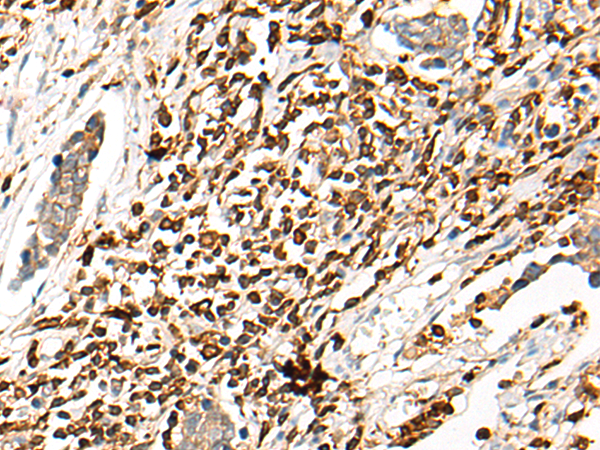

The image is immunohistochemistry of paraffin-embedded Human liver cancer tissue using 47239(WWTR1 Antibody) at dilution 1/35. (Original magnification: ?00)

,

The image is immunohistochemistry of paraffin-embedded Human lung cancer tissue using 47239(WWTR1 Antibody) at dilution 1/35. (Original magnification: ?00)